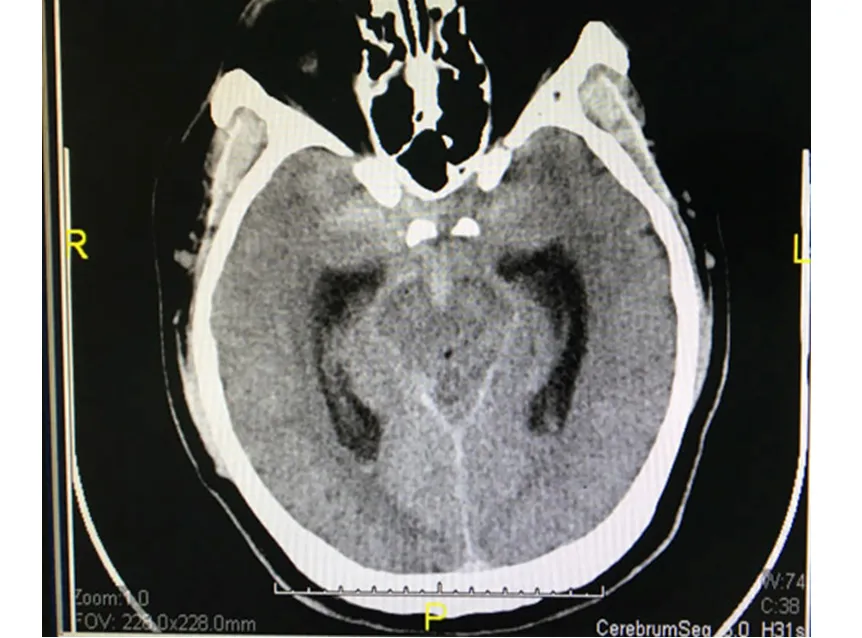

Hình ảnh cho thấy ông H. bị xuất huyết màng não. Ảnh: CTV

Kết quả cho thấy ông H. bị xuất huyết màng não, xuất huyết trong các não thất và bể dịch não-tủy ở nền sọ, viêm đa xoang. Ông H. nhanh chóng được can thiệp giúp ngưng chảy máu vì nghi ngờ vỡ túi phình dị dạng mạch máu não.